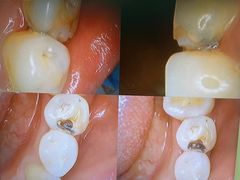

• 爱贝口腔·牙周诊疗·种植修复中心

• -爱贝口腔·牙周诊疗·种植修复中心